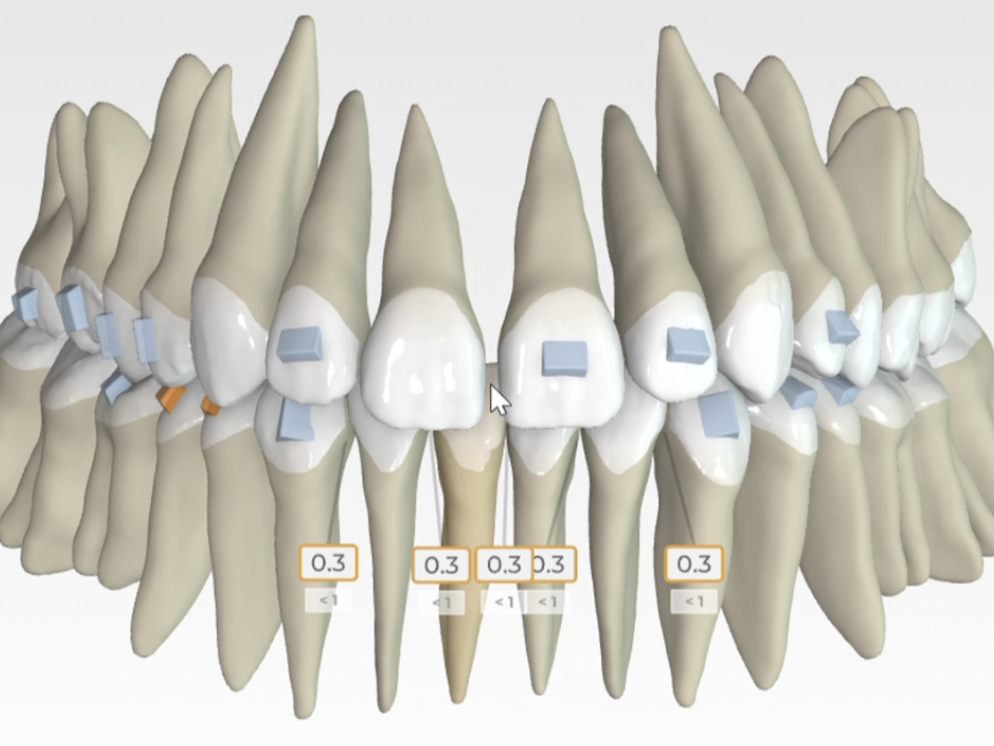

Fiecare pacient este diferit, motiv pentru care nu există o soluție universală pentru toate cazurile ortodontice. După analiza clinică și interpretarea investigațiilor necesare, discutăm toate opțiunile disponibile și recomandăm varianta care oferă cel mai bun echilibru între sănătate, estetică, confort și predictibilitate.

În anumite situații, tratamentul poate începe imediat. În altele, cea mai bună alegere poate fi monitorizarea evoluției sau amânarea intervenției până la momentul optim. Scopul consultației este ca pacientul să înțeleagă clar diagnosticul, beneficiile și limitările fiecărei opțiuni, precum și etapele necesare pentru obținerea rezultatului dorit.

În cadrul consultației discutăm și durata estimată a tratamentului, tipurile de aparate dentare potrivite, costurile implicate și pașii următori, astfel încât decizia să fie luată informat și în deplină cunoștință de cauză.